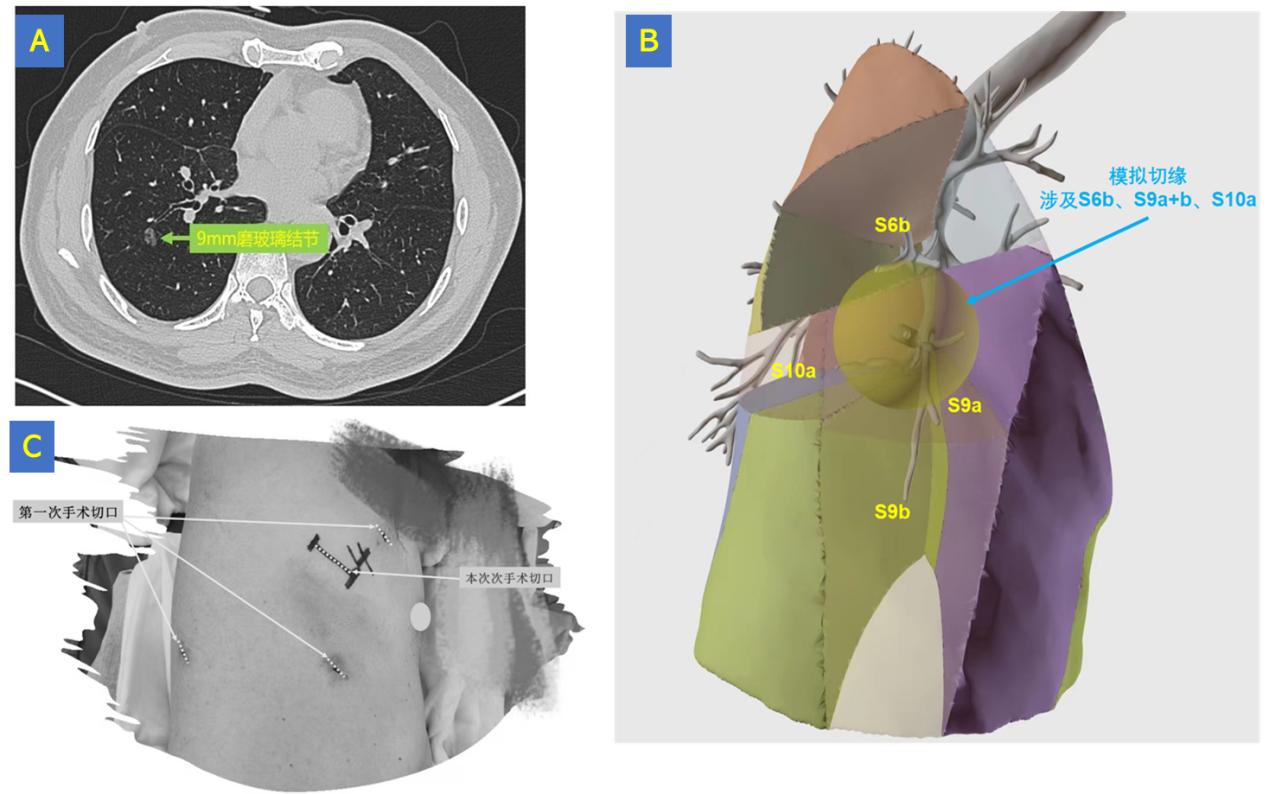

患者是一位58岁的中年男性,两年前体检发现右肺上叶8mm和右肺下叶6mm共两枚磨玻璃结节,于当地医院行“胸腔镜(三孔)右肺上叶楔形切除+淋巴结清扫术”,术后病理诊断为右肺上叶中分化腺癌。今年6月,患者复查胸部CT提示右肺下叶磨玻璃结节较前明显增大至9mm,综合考虑下叶结节亦高度怀疑肺癌,患者及家属决定再次接受手术切除治疗。

然而,患者右肺下叶结节位置较深,且位于背段、外基底段、后基底段交界区,无论切除哪一肺段均难以保证足够的安全切缘,患者及家属辗转全国多家医院,均被告知要想切除肿瘤只能将整个右肺下叶切除。患者及家属慕名辗转来到四川大学华西医院,求助胸外科刘伦旭教授团队。

由于患者既往已行右肺上叶大部分切除,倘若再切除整个右肺下叶,那么患者右肺将仅剩一个中叶和部分上叶,对患者今后的生活质量势必会造成显著影响。为了在既完整切除肿瘤并保证足够安全切缘的同时,又为患者争取保留更多的健康肺组织,刘伦旭教授、蒲强教授和刘成武副教授团队对患者的影像进行了仔细分析,并采用三维重建技术将患者的 肺结节、支气管、肺动静脉等关键结构进行可视化呈现,经过周密分析和讨论,最终为患者制定了右下肺背段b亚段+外基底段+后基底段a亚段(RS6b+9+10a)联合切除方案。

A. 胸部CT显示患者右肺下叶结节位于背段、外基底段、后基底段交界区;

B. 术前采用三维重建技术行精准手术规划;

C. 手术切口